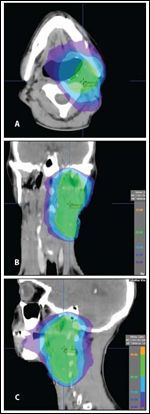

FIGURE 2

Re-irradiation Planning Images for the Second Locoregional Relapse in a Patient With a Stage IVA HPV-Positive Squamous Cell Carcinoma of the Head and Neck

DR. RABEN: Following 2 cycles of TP chemotherapy, we elected to treat this patient with SBRT to 25 Gy delivered in 5 fractions (Figure 2), with sensitizing cetuximab during therapy and for a month afterwards. He had stable disease during treatment, but his disease progressed 2 months after he finished therapy.